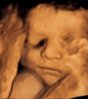

Min lille ser ut som har skikkelig overbitt (eller snusleppe som noen kalte det); så ja ;)

Veldig klart og fint 3D-bilde, forresten :)

Ja det var veldig klart og fint kjempe gøy å se.

Så fint å høre at det var fler som har babyer med snusleppe.. Hehehe..